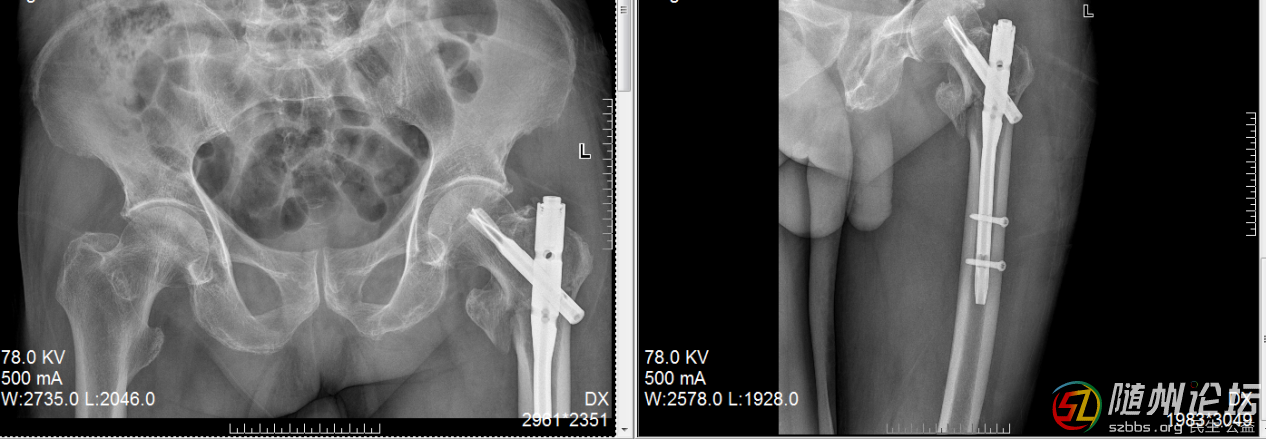

另一位送錦旗的,是一位年過八十的老奶奶,她不慎摔傷了髖部??紤]到患者年紀(jì)大、基礎(chǔ)疾病多,創(chuàng)傷骨科啟動多學(xué)科會診(MDT),為其制定了完全個性化的手術(shù)及康復(fù)方案。沒有采用“一刀切”的模式,而是綜合評估其身體狀況、生活需求及家庭支持,選擇了創(chuàng)傷最小、最適合的微創(chuàng)髓內(nèi)釘固定,并結(jié)合中西醫(yī)結(jié)合的康復(fù)理念,術(shù)后早期運(yùn)用中藥熏蒸等手段活血化瘀、消腫止痛。術(shù)后早期功能鍛煉,顯著改善了患者的舒適度,縮短了臥床時間,有效預(yù)防了并發(fā)癥,讓老人能重新站立行走。